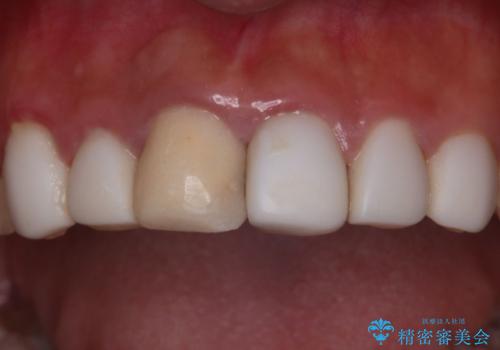

- セラミッククラウン

- 2009~2025年6月

- 000本

最新の症例

Latest cases